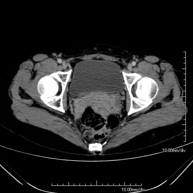

Prova diagnòstica que consisteix en obtenir imatges bi i tridimensionals de la pelvis d'alta definició anatòmica (estructures òssies, estructures vasculars, bufeta, úter i ovaris, pròstata i vesícules seminals, urèters, etc.) mitjançant l'ús d'un equip de TC (Tomografia Computeritzada). La majoria d'estudis requereixen l'ús de contrast iodat. - TC Abdominopèlvic